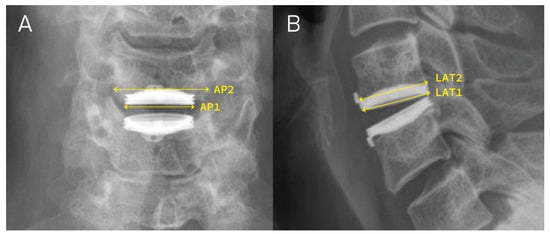

2.3. Calculation